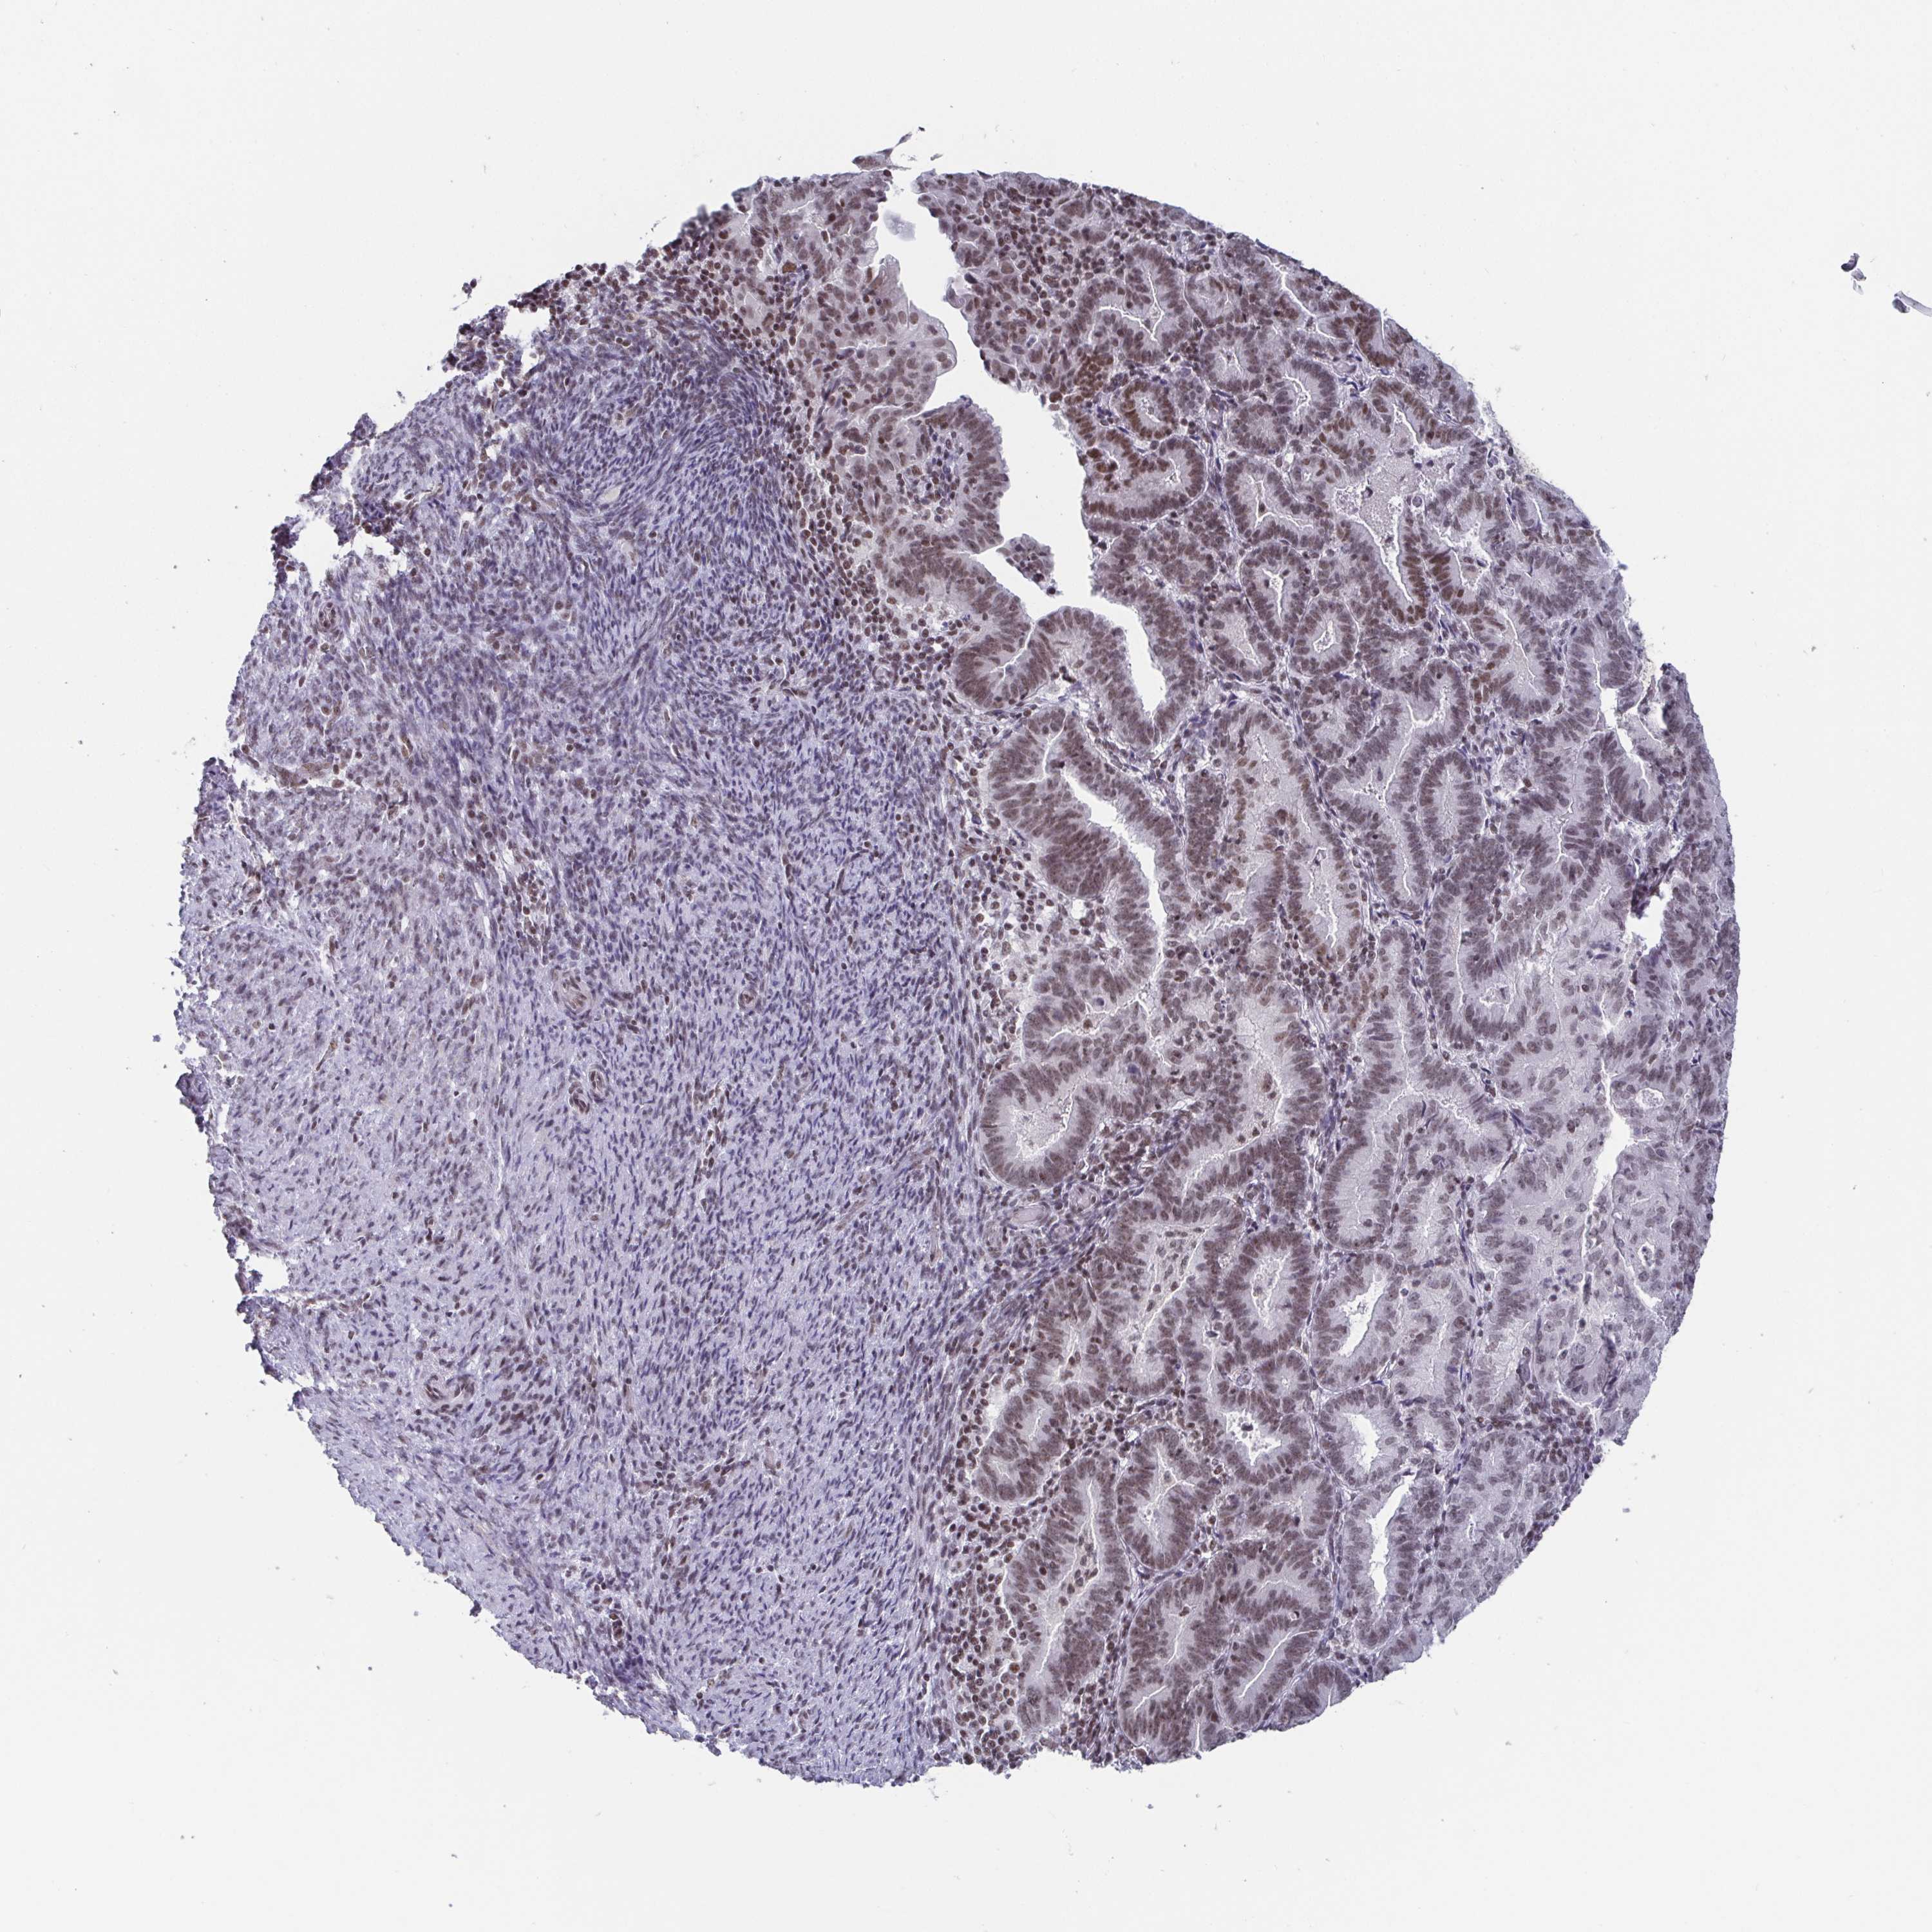

ENDOMETRIAL CANCER - Protein expressioni

A mouse-over function shows sample information and annotation data. Click on an image to view it in a full screen mode. Samples can be filtered based on level of antibody staining by selecting one or several of the following categories: high, medium, low and not detected. The assay and annotation is described here.

Note that samples used for immunohistochemistry by the Human Protein Atlas do not correspond to samples in the TCGA dataset.

Antibody stainingi

Antibody staining in the annotated cell types in the current human tissue is reported as not detected, low, medium, or high, based on conventional immunohistochemistry profiling in selected tissues. This score is based on the combination of the staining intensity and fraction of stained cells.

Each image is clickable and will lead to virtual microscopy that enables deeper exploration of all samples and also displays staining intensity scores, fraction scores and subcellular localization as well as patient and tissue information for each sample.

Antibody HPA004122

Antibody CAB062550

Antibody CAB068181

Antibody CAB068182

Staining

High

Medium

Low

Not detected

Intensity

Strong

Moderate

Weak

Negative

Quantity

>75%

75%-25%

<25%

None

Location

Nuclear

Cytoplasmic/membranous

Cytoplasmic/membranous,nuclear